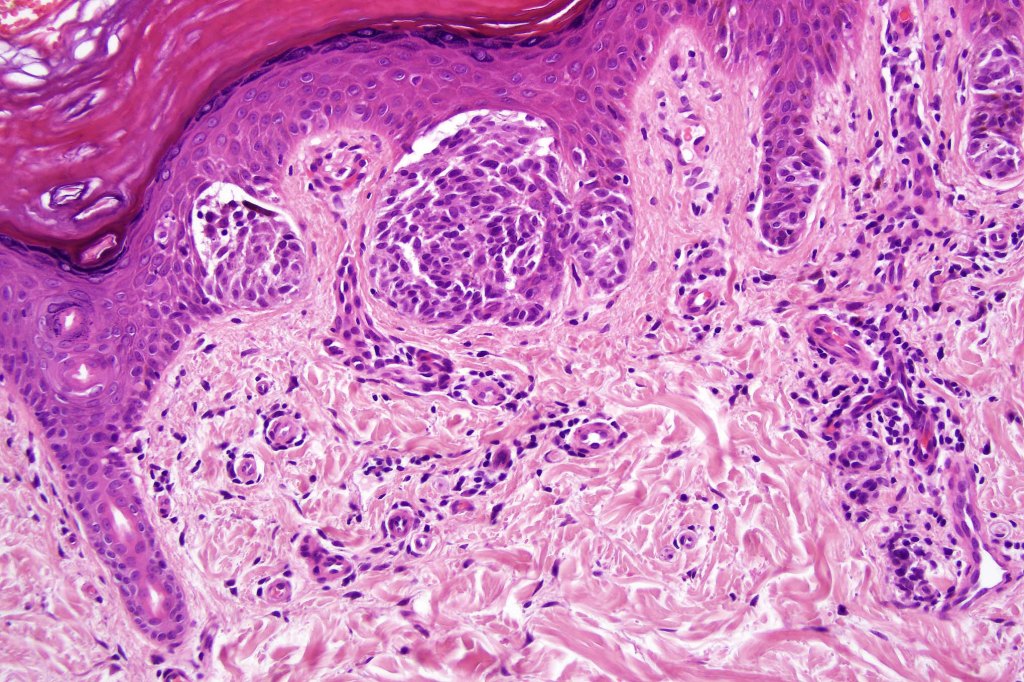

Combined common & deep penetrating nevus